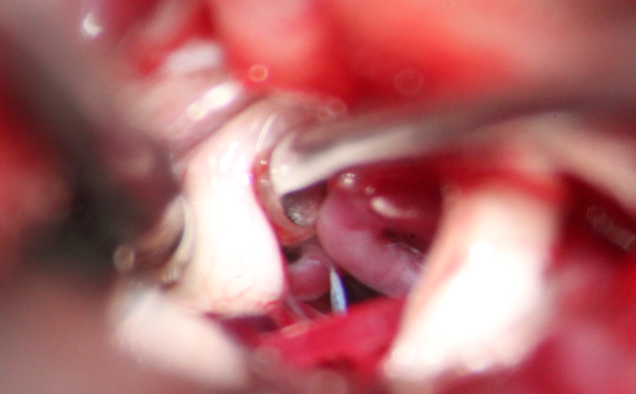

在做好充分的术前准备之后,我的团队为李叔做了三叉神经显微血管减压术。下面两张图,就是手术中显微镜下看到的样子。

图片

图片【在三叉神经根(白色的)附近放上医用垫棉,隔开血管团(红色的),为神经减压。医院供图】